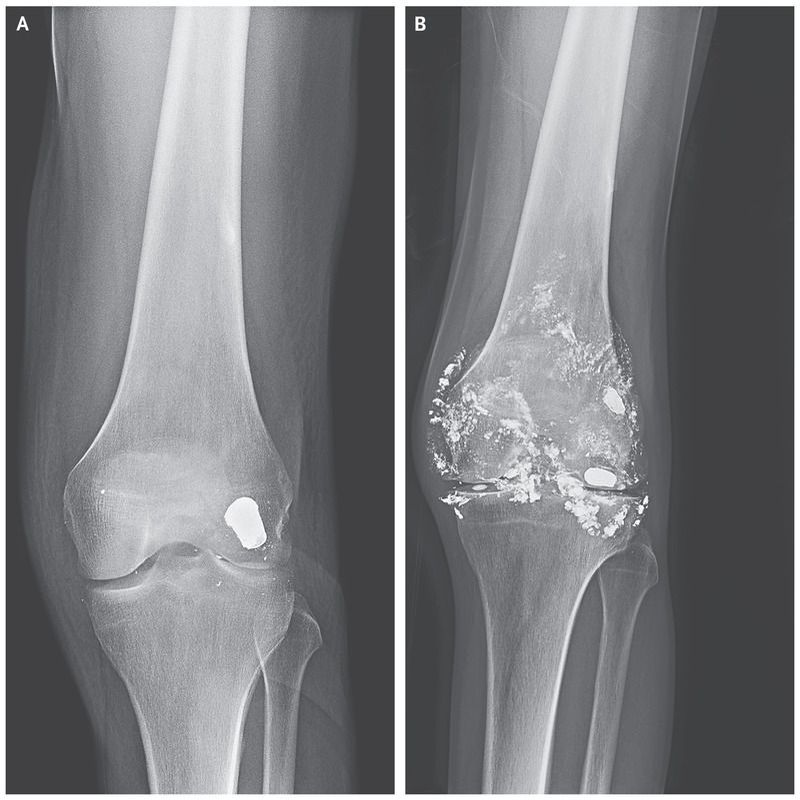

A 46-year-old man presented to the emergency department with worsening chronic left knee pain. Fourteen years before presentation, he had sustained a gunshot wound to the left knee. Radiographs obtained at the time of that injury showed a metallic bullet embedded in the posterior weight-bearing surface of the lateral femoral condyle and metallic debris within the joint (Panel A). No surgery was performed to remove the bullet at that time. At the current presentation, the physical examination was notable for a large effusion in the left knee. Repeat radiographs showed that, in addition to changes consistent with arthritis in the joint, the bullet had fragmented into metallic particles throughout the joint and synovium (Panel B). Laboratory studies revealed microcytic anemia, with a hemoglobin level of 9.1 g per deciliter (normal range, 12.9 to 16.8), and an elevated blood lead level (182 μg per deciliter [8.8 μmol per liter]). The Mini–Mental State Examination score was 24 (scores range from 0 to 30, with lower scores indicating poorer cognitive performance). The patient showed no other symptoms of chronic lead poisoning. Intraarticular bullets should be removed surgically at the time of the injury. In addition to causing joint damage, intraarticular bullets can fragment and dissolve in synovial fluid, leading to lead absorption and delayed symptomatic lead poisoning. The patient received chelation therapy. Surgical management with a left knee synovectomy was planned, but the patient left the hospital before surgery and was lost to follow-up.